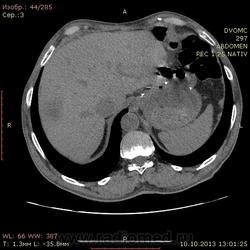

69 лет. КТ контроль от августа. Посте очередного курса химии. Начало истории здесь http://www.radiomed.ru/cases/kt-bryushnoi-polosti-adenokartsinoma-zheludka-sostoyanie-posle-rezektsii-zheludka-mts-v-pechen

Сегодня выглядит так. DICOM здесь http://files.mail.ru/2A18DCE6A6AA4546B51713D2F9C9E91A

На мой взгляд метастазов новых нет, но старые увеличились и один из пораженных л\у также увеличился.